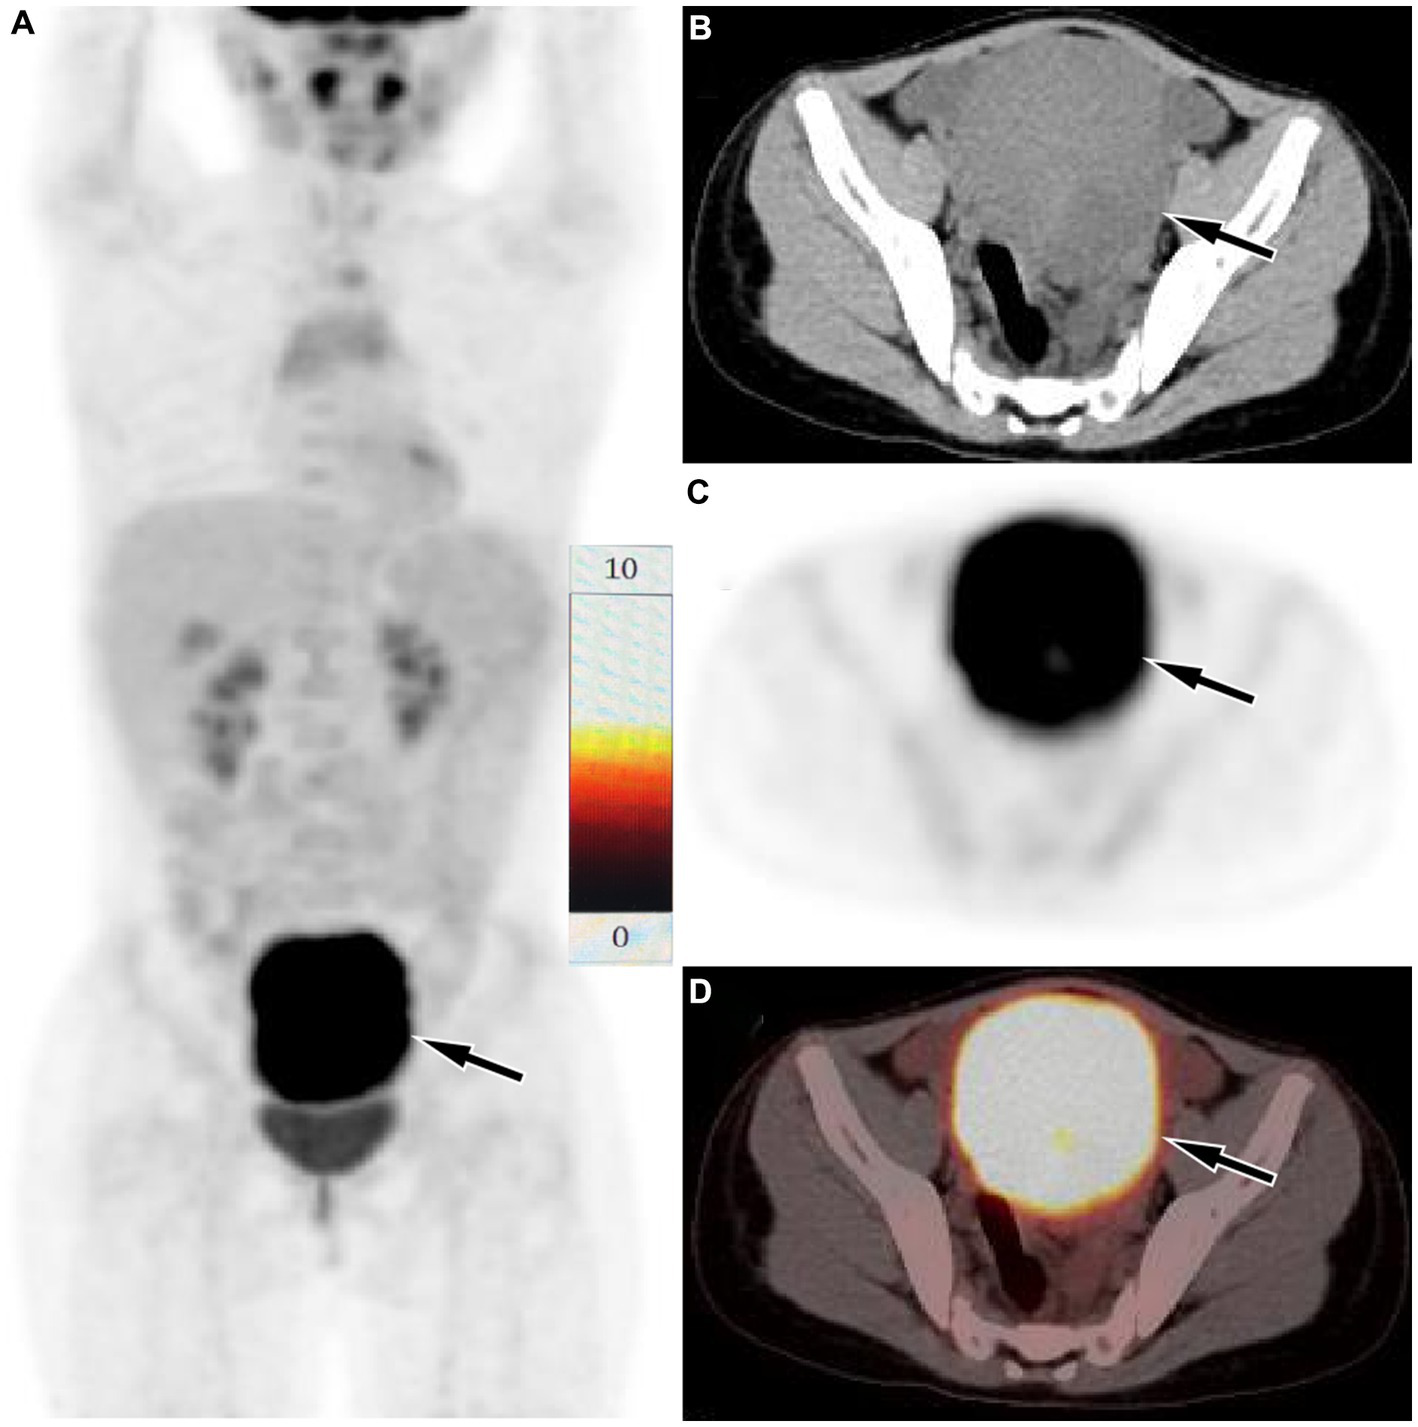

Figure 2

Fluorine-18 fluorodeoxyglucose (18F-FDG) positron emission tomography (PET)/CT imaging of the patient. The maximum intensity projection (MIP, A) showed a significantly increased 18F-FDG uptake in the lower abdominal area (arrow). Axial CT (B), PET (C) and PET/CT fusion (D) showed that the lesion with significantly increased 18F-FDG uptake, with a SUVmax of 9.3 (arrows), which was located in the serosal surface of the sigmoid colon, and the adjacent intestinal tube is compressed, the proximal intestinal tube is dilated, and liquid exudation shadow is seen around the mass, and a small amount of fluid is seen in the pelvic cavity.